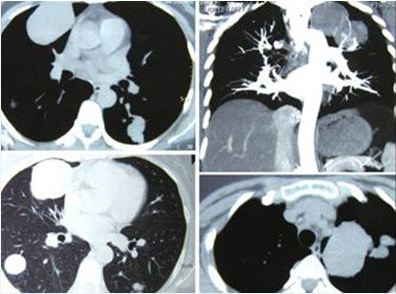

Alex (not real name) is 63 years old. His problem started about 3 years ago, in 2012 while visiting Australia he had severe pain in his right forearm. He was admitted into a hospital. An X-ray showed a growth in his lung. On returning home, Alex had a biopsy and was told that he had a high-grade undifferentiated soft tissue sarcoma in the right chest. The tumour was lodged behind the sternum but had spread onto the first rib. It was stage 3 cancer.

Alex underwent chemotherapy in December 2012. The regime used was Doxorubicin and Ifosfamide. The tumor shrank a bit. Then Alex had a surgery. This operation was done in a heart hospital in early 2013. During this surgery the doctor also did a by-pass for his heart. (Note: Alex underwent an angioplasty in the same hospital in 2004).

After the surgery, Alex had 36 sessions of radiotherapy.

A small tumor on the first rib was not removed during the surgery and this started to grow again. Alex underwent another surgery in June 2014. This time the surgery to remove the first rib and part of second rib was done in Singapore. After the surgery, Alex received another 36 sessions of radiation in October 2014 in a Malaysian hospital.

Hardly 2 months later, the tumor spread to the right lung membrane, spewing fluid into three-fourth of his right lung. Alex had to be hospitalised and fluid was tapped out. This happened in late in November 2014.

A CT scan in mid-March 2015, showed no improvement and the drug treatment was stopped on 26 March 2015.